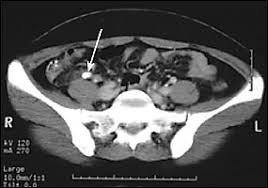

It is used to define normal and abnormal structures in the what does a ct scan show?

Diagnostic Accuracy Of North America Expert Consensus Statement On Reporting Ct Findings In Patients Suspected Of Having Covid 19 Infection An Italian Single Center Experience Radiology Cardiothoracic Imaging

Diagnostic Accuracy Of North America Expert Consensus Statement On Reporting Ct Findings In Patients Suspected Of Having Covid 19 Infection An Italian Single Center Experience Radiology Cardiothoracic Imaging from pubs.rsna.org